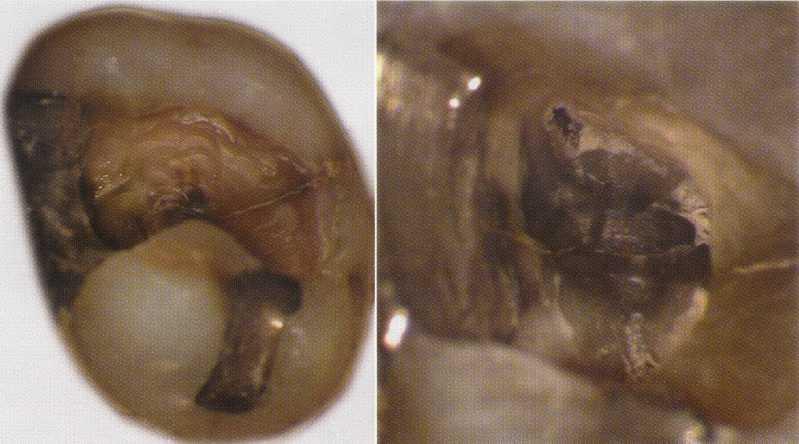

FIGURE 2-13 A, Removal of the amalgam permits inspection of the tooth for fractures. The use of microscopy allows identification of a mesiodistal fracture. The pulp chamber has not been entered. B, On entering the pulp chamber, the clinician notes a fracture across the pulpal floor from mesial to distal. Wedging a Glick instrument into the access allows the clinician to visualize the fracture spreading and closing in this hopeless tooth. Although this gross fracture was visible with loupes, the extent of many fractures cannot be seen. Diagnosis and prognostication then become guessing games at best. Note the white dot of the MB2 canal located (in vain) with a Mueller bur above the fracture about halfway between the fracture and the MB canal; this was not visible without the microscope.